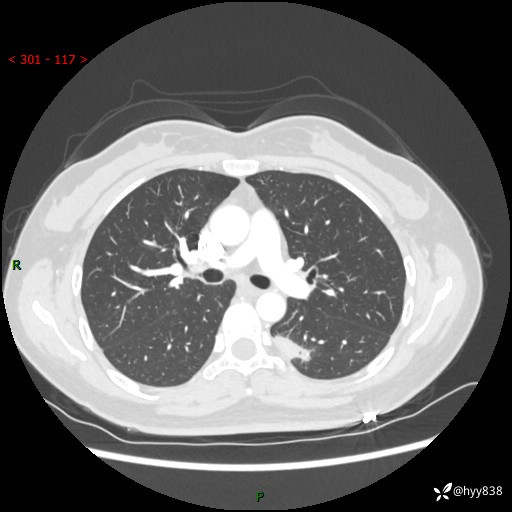

【患者信息】:36岁/女

【主诉】:左侧下胸部阵发性疼痛2周,乏力1周

【现病史及既往史】:患者自诉2周前饮酒后出现左侧下胸部阵发性疼痛,不随呼吸改变,无咳嗽咳痰、头晕头痛、咳血、呼吸困难等不适,于当地第一人民医院查胸部CT提示肺部感染,随后前往我院门诊给予抗感染(左氧氟沙星)治疗1周,自诉胸痛较前好转,感乏力、头晕,偶尔干咳,无咳痰,无发热、畏寒、胸闷、咯血、四肢酸痛、腹泻、腹痛等不适,门诊复查胸部CT提示:左肺下叶感染,病灶较前增加增大,遂以“肺部感染”收入我科。 起病以来,患者精神、饮食、睡眠可,大小便正常,体力体重无明显变化。

【检查】:胸部CT增强(外院平扫)